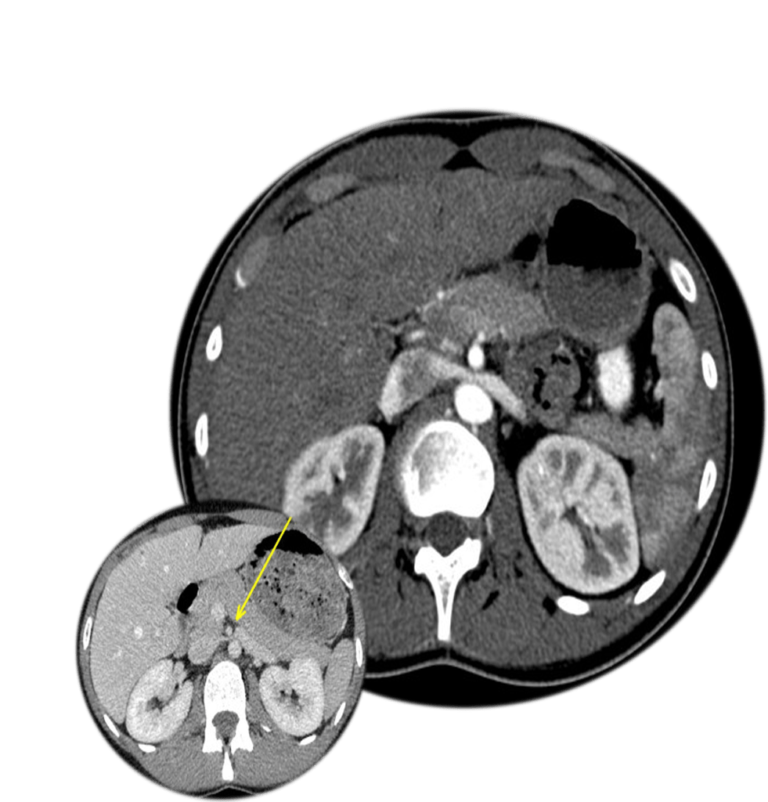

From radiopaedia.org

Nutcracker syndrome (annotated CT) Image Nutcracker Syndrome Fatigue the nutcracker syndrome is characterized by a group of clinical. nutcracker phenomenon refers to compression of the left renal vein, most commonly between the aorta and the. patients can be referred to a vascular surgeon due to symptoms and/or radiologic findings. nutcracker phenomenon refers to compression of the left renal vein, most commonly between the. . Nutcracker Syndrome Fatigue.